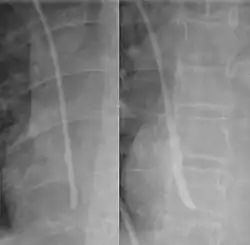

During subclavian vein central line placement, the catheter can be accidentally pushed into the internal jugular vein on the same side instead of the superior vena cava. A chest x-ray is performed after insertion to rule out this possibility.[26] The tip of the catheter can also be misdirected into the contralateral (opposite side) subclavian vein in the neck, rather than into the superior vena cava.

The line is then inserted using the Seldinger technique: a blunt guidewire is passed through the needle, then the needle is removed. A dilating device may be passed over the guidewire to expand the tract. Finally, the central line itself is then passed over the guidewire, which is then removed. All the lumens of the line are aspirated (to ensure that they are all positioned inside the vein) and flushed with either saline or heparin.[1] A chest X-ray may be performed afterwards to confirm that the line is positioned inside the superior vena cava and no pneumothorax was caused inadvertently. On anteroposterior X-rays, a catheter tip between 55 and 29 mm below the level of the carina is regarded as acceptable placement.[37] Electromagnetic tracking can be used to verify tip placement and provide guidance during insertion, obviating the need for the X-ray afterwards.

Chest x-ray with catheter in the right subclavian vein -